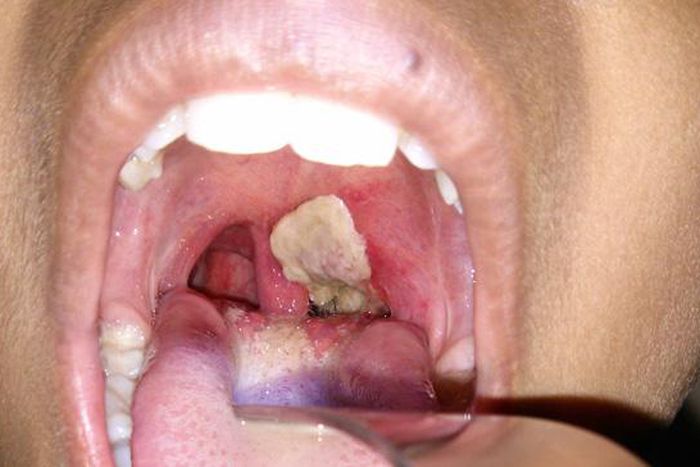

The Nigeria Centre for Disease Control (NCDC) says no fewer than 1,191 persons have been killed by diphtheria from May 2023 to date across Nigeria.

He said the country recorded suspected cases of more than 38,000 persons while the number of confirmed cases stood at 23,000.